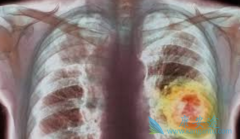

• 印度易瑞沙/吉非替尼的副作用里最严重的是间质性肺炎

印度易瑞沙/吉非替尼的副作用里最严重的是间质性肺炎

我们知道 易瑞沙 的副作用里最严重的是间质性肺炎,因为有致命的危险,那么易瑞沙(吉非替尼)引起间质性肺炎的几率有多大呢?全球因易瑞沙(吉非替尼)所导致的间质性肺炎的平均发病率约1%,在我国的发病率更低,只有0.5%。至于由易瑞沙(吉非替尼)引 ...